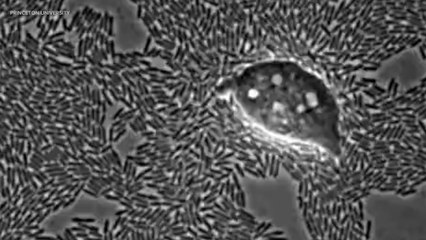

The bacteria releases a toxin that causes the outer epidermis to die and shed, leaving raw exposed flesh. Children are particularly susceptible as their immune systems are not fully developed and reduced kidney function can also increase chances of becoming infected, the disease can be cured with oral antibiotics.br br Unfortunately, because Ben was misdiagnosed with having an allergic reaction to antibiotics he was taken off them for over 18 hours, which led to the bacteria spreading into his bloodstream and throughout his entire body.br br Victims can die of secondary infections or dehydration as fluids and electrolytes are lost as the skin falls away. Thankfully, after 3 weeks of treatment Ben is recovering. He will be left scarred and has some difficulties with mobility as his new skin is still too tight, but his mom said she’s happy to finally be able to hug and comfort her little boy.br br ----------------------------------------­---------------------br br Welcome to TomoNews, where we animate the most entertaining news on the internets. Come here for an animated look at viral headlines, US news, celebrity gossip, salacious scandals, dumb criminals and much more! Subscribe now for daily news animations that will knock your socks off.